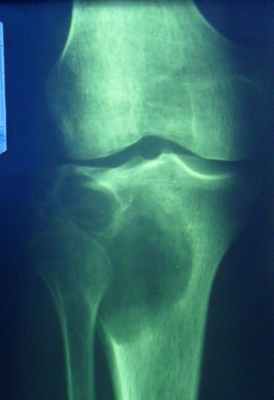

16. Остеосаркома

• Клиника – боли, припухлость в области

сустава. Местная гипертермия в области

сустава

• Локализация – типично поражение костей

коленного сустава в зоне метафиза (у

молодых трубчатые кости, взрослые

трубчатые и плоские, пожилые чаще

плоские)

17. Рентгенсемиотика остеобластической остеосаркомы

• Склерозирование

патологического очага не

распространяющееся на

ростковую зону

• Кортикальный слой

разрушен, есть

«периостальный козырек»,

спикулы